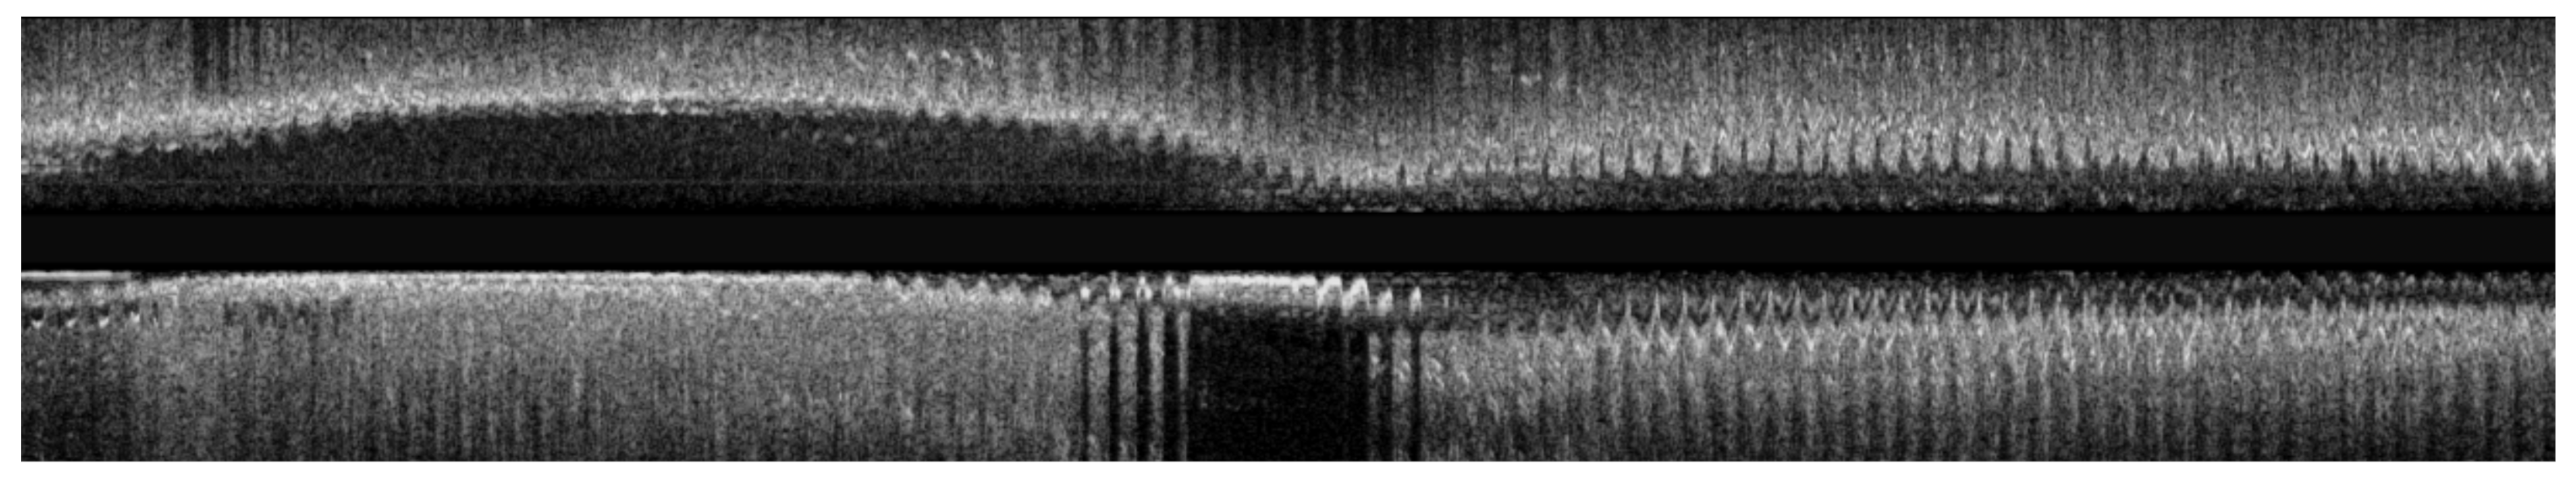

On the other hand, temporal IVUS image pullbacks suffer from artifacts and image variations that are caused by cardiac pulsation, which can complicate their analysis rendering the comparison of temporal datasets hard. First, the transducer is affected by an oscillation in the longitudinal axis, due to the periodic cardiac muscle contraction and expansion. Such oscillations result in some vessel’s cross-sections to be sampled multiple times during one pullback, which can be observed as sawtooth-like artifacts in the longitudinal reconstruction of the pullback [1], as seen in Figure 1. In addition, heart contraction causes a non-rigid deformation of the vessel due to its compliance. As a result the appearance of a given IVUS cross-section depends on the sampling instant with respect to the heart cycle. Therefore, to compare the same cross-section of the vessel over time, it is essential to select the corresponding frames with regard to the cardiac cycle. Moreover, due to the catheter being withdrawn through the blood vessel, its axial position with respect to the vessel is not fixed and the catheter freely moves inside it leading to rotational inconsistencies between temporal acquisitions. As a consequence, some vessel sections may be captured multiple times while several frames might be misaligned both longitudinally and axially.

Figure 1. Sagittal views of an IVUS pullback prior to the sub-sampling of the frames corresponding to the end-diastolic cardiac phase.

As discussed in the introduction, the contraction and expansion of the heart muscles lead to periodical deformations of the vessel structures as well as to longitudinal oscillation of the IVUS catheter. As a result, the captured imaging sequences suffer from time varying deformations and repetitive frames across the entire section of the vessel, which depend on the cardiac cycle (Figure 1). In order to reduce these effects and address the heart cycle dependent vessel appearance, a downsampling method on the IVUS pullback is applied through a gating method. The rationale is that by sampling frames at a given point of the cardiac cycle, the resulting pullbacks convey more consistent vessel morphology information [1]. Various gating methods based on electrocardiogram (ECG) signals have been developed and effectively applied to such pullbacks. By analyzing the ECG signal either during the procedure (online) or afterwards (offline), the heart cycle can be accurately determined and frames that correspond to a particular point of the cardiac cycle can be selected [11]. When the ECG signals cannot be obtained or when they are noisy and thus do not perform well, a ECG-like signal can derive by analyzing the IVUS pullbacks themselves [12]. Finally, when none of the above signals are present, the sub-sampling can be performed manually by an expert physician. In this study, for the pullbacks, the reference time point of the heart cycle was the end-diastolic phase, during which the heart is almost stationary, while those images that did not correspond to the end-diastolic phase of the cardiac cycle were not included in the dataset. As a result, the coronary arteries, which are located on the surface of the heart, are relatively immobile at the end-diastolic phase. Having achieved this important data preparation step, the proposed algorithm is designed to address the remaining problems regarding multiple frames of the same anatomical area and rotational inconsistencies.